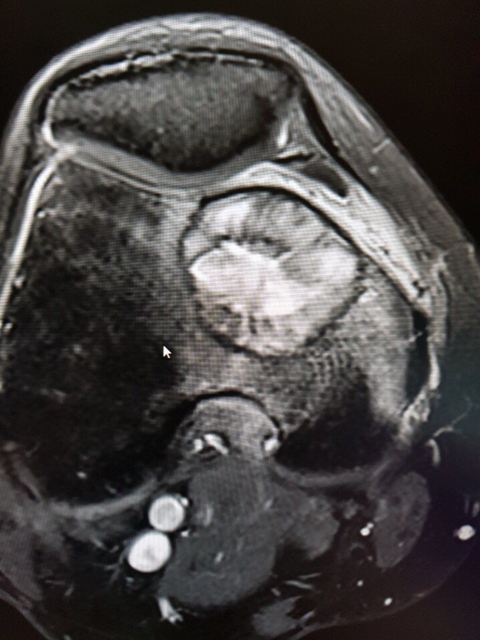

거대세포종 위치와 수술부위는 아래와 같구요...

골시멘트채우고 뼈강도 보강을 위해 철판을 댔다고 합니다.

• 작성자소중한분 작성자 본인 여부 작성자 | 작성시간 18.10.25 오늘 수술후 외래 다녀왔는데 다 나은거라네요~ 수술후 사진보니까 무시무시하네요~ 관절운동 걷기운동 서서히 시작 하라고 합니다. 통증은 일종의 신경통으로 수술로 무릎을 지나는 신경들이 잘려서 여기저기 날카로운 통증이 올수 있디고 합니다. 제가 올렸던 글이 다른 분들께도 참고가 되기를 바랍니다. 댓글 첨부 이미지 이미지 확대